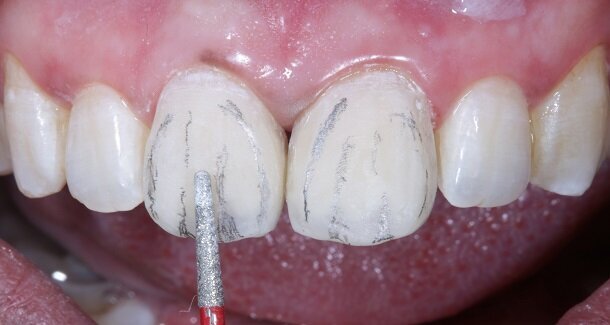

Fig 13 and 14 -Transitional Line angles were marked using a pencil and made prominent using medium grit 3M Soflex Discs proximally. The apparent faces of both the teeth were thus, created.

Fig 15 and 16 - For the surface texture; vertical surface macro-anatomy showing developmental grooves (mesial and distal) were marked using a pencil and created using the red ring finishing bur.

Fig 17- Horizontal surface micro-anatomy, that is, the Perikymata or imbrication lines were marked cervically and incisally, using a pencil and created using the red ring finishing bur.